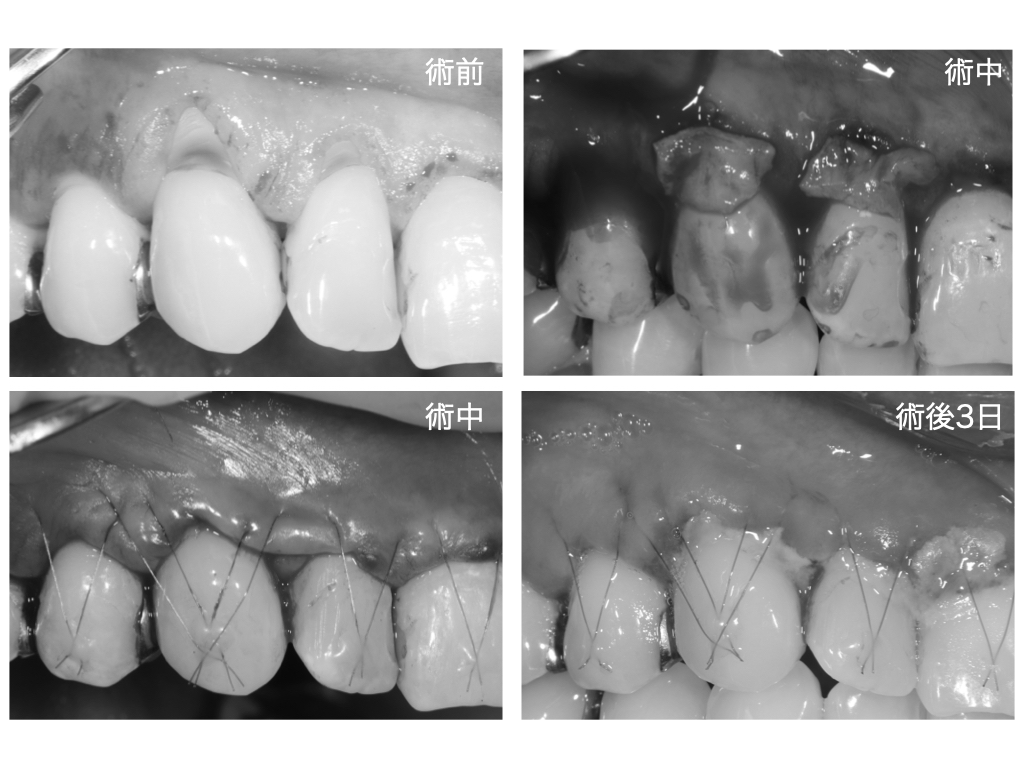

治療内容

今回行ったのは

CTG(結合組織移植術)を併用した根面被覆術です。

治療のポイント

・露出した歯根面を覆うために歯肉を移動

・口蓋から採取した結合組織を移植

・歯肉の厚みを増やし、長期安定を図る